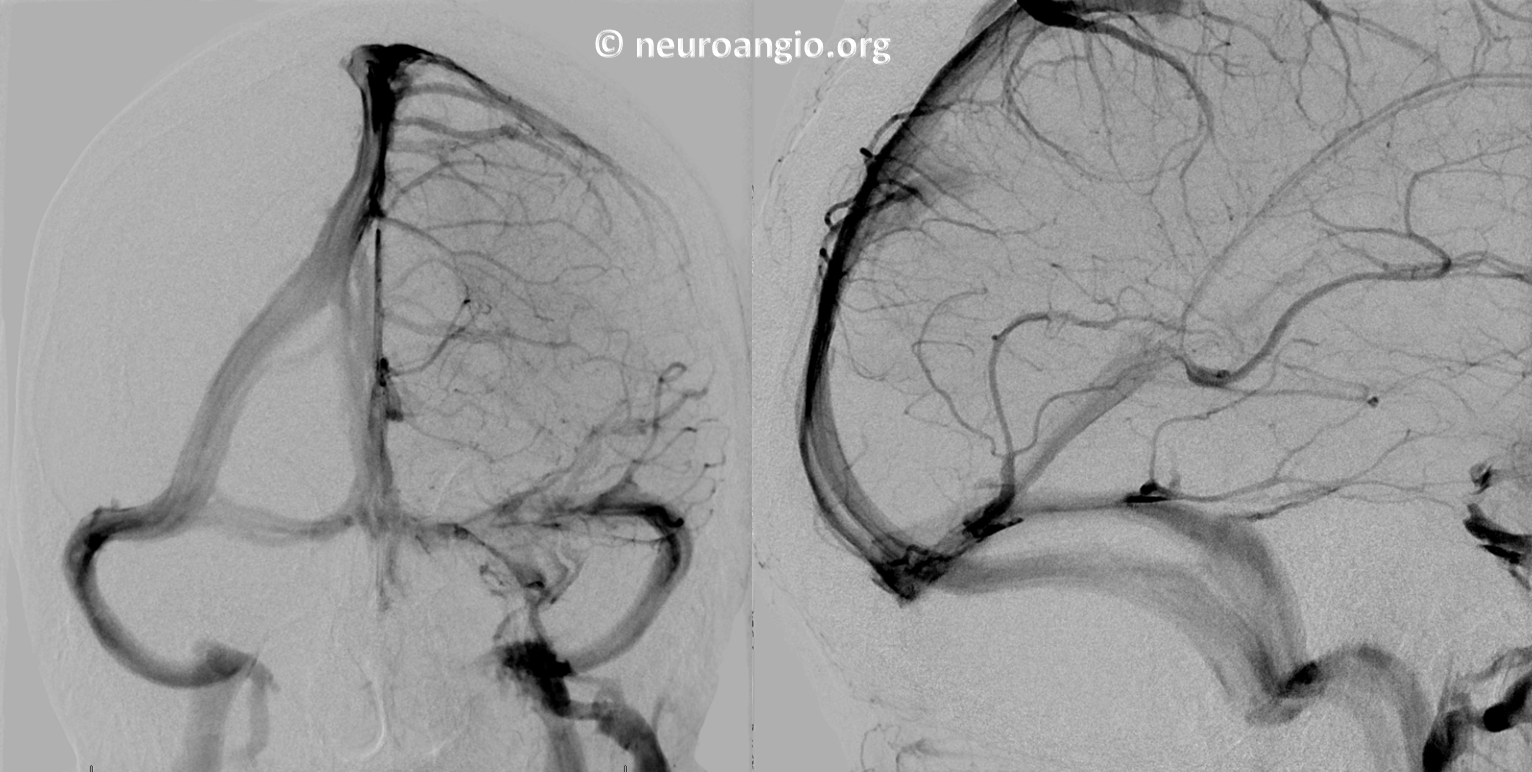

Following embolization, resection, recurrence (as frequently the case with childhood AVMs) and gamma-knife, things look good. Stereo, of course.

Following embolization, resection, recurrence (as frequently the case with childhood AVMs) and gamma-knife, things look good. Stereo, of course.